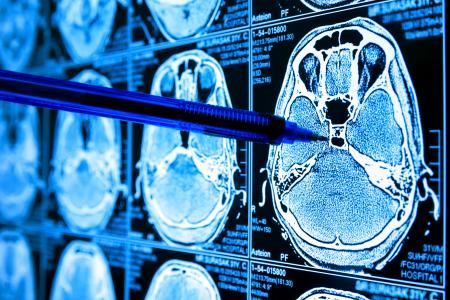

GLIOBLASTOME : Une régression spectaculaire avec une nouvelle thérapie « CAR-TEAM »

Ces résultats préliminaires d'essai clinique de phase I, publiés dans le New England Journal of Medicine font état d’une régression « spectaculaire et rapide » du glioblastome (GMB) après une thérapie CAR-T de nouvelle génération. L’essai mené au Mass General Brigham (MGB) Cancer Center révèle ainsi une toute nouvelle approche CAR-T, avec des cellules « CAR-TEAM » qui ciblent des populations cellulaires mixtes au sein des tumeurs.

L’étude, menée dans le cadre d’un projet collaboratif visant à apporter les promesses de la thérapie cellulaire aux patients atteints de glioblastome, apporte des résultats spectaculaires chez les premiers patients à recevoir ce nouveau traitement. L’article fait état des résultats de 3 premiers cas de patients, suivis par un essai clinique de phase I. L'essai, connu sous le nom d'INCIPIENT, visait, principalement, à évaluer l'innocuité des cellules T CARv3-TEAM-E chez ces patients atteints de GBM récurrent. Tous les patients avaient été traités par radiothérapie standard et chimiothérapie au témozolomide et ont été inclus dans l'essai après une récidive de la maladie. L’essai révèle que :

- quelques jours seulement après un seul traitement, les patients bénéficient

d’une réduction spectaculaire de leurs tumeurs,

- un patient ayant atteint une régression tumorale presque complète.